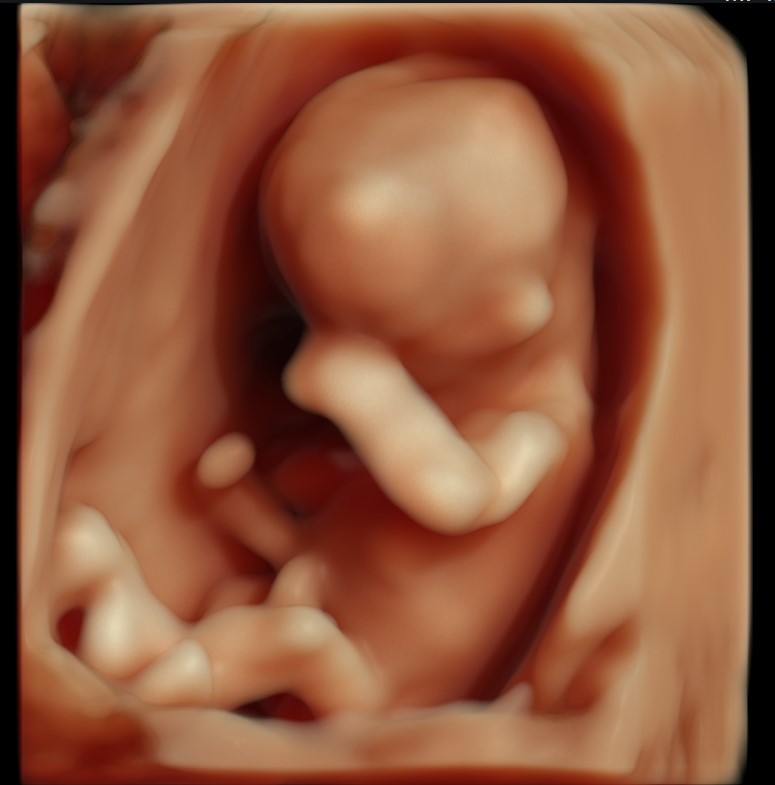

S návštevou u pani doktorky som bola veľmi spokojná, bola milá, profesionálna, počas celého vyšetrovania všetko vysvetlovala. Napriek momentálnej pandemickej situácii partner bol celý čas so mnou pri vyšetrení. Mali sme pekný spoločný zážitok zo sledovania nášho bábätka. Pani doktorku vrelo odporúčam.